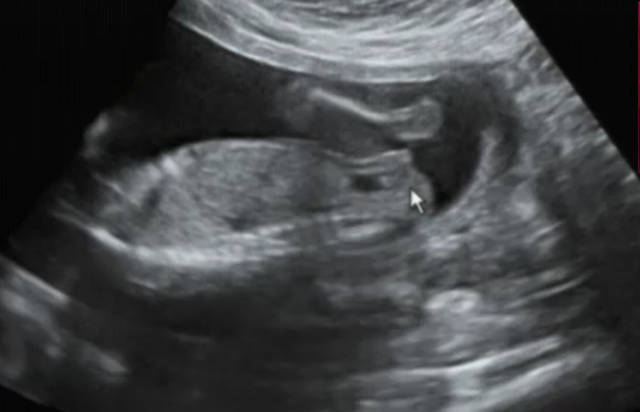

Image bébé 16 semaines de grossesse

Image bébé 16 semaines de grossesse- 16 semaines de grossesse 159 jours vous séparent de la rencontre avec bébé Où en estil de son développement ?Voici ce à quoi vous pouvez vous attendre à 16 semaines de grossesse, y compris les nouveaux symptômes de grossesse que vous pourriez rencontrer Bébé à 16 semaines de grossesse Les statistiques de votre bébé cette semaine mesurant de 4 à 4, 5 pouces de hauteur de croupe et basculant la balance à 3 ou 4 onces

16 semaines de grossesse bébé pèse presque 0 g À la 16ème semaine de grossesse, vous venez de dépasser le premier trimestre Votre bébé a maintenant 4 mois et sa taille avoisine les 16cm pour un poids minimum de 150g Pendant cette période, la tête prend du volume et dépasse les dimensions du corps du fœtus La 16ème semaine de grossesse correspond à 18 SA du 4ème mois de grossesse Que va t'il se passer pour vous et votre bébé durant cette semaine ? Aussi, à 16 semaines de grossesse, le fœtus accumule des graisses et affermit la peau En ce qui concerne l'organogenèse, elle arrive à maturité durant cette semaine Si auparavant, les intestins de bébé ne pouvant pas encore à assurer entièrement son rôle, désormais, ils sont parfaitement opérationnels

Québec tous les articles Grossesse Choisir le nom de bebe Votre grossesse, étape par étape En français la grossesse (vidéos) 16 semaines de grossesse Écrit pour BabyCenter Canada 3 Dart, LLC for BabyCenter In this article Comment se développe votre bébé En cette 16ème semaine de grossesse (18 SA), le bébé mesure 17 cm et pèse 160 g Ses différents organes poursuivent leur maturationIl a maintenant de jolies oreilles qui encadrent son visage Ses paupières sont toujours fermées mais il est sensible à la lumière Un fin duvet que l'on appelle lanugo recouvre son corps et tombera à la naissance

Calendrier de grossesse la 16e semaine de grossesse (18e SA) Du haut de ses 18 cm (de la tête aux talons) et 160 g environ, votre bébé continue de grandir Quand à vous, pleine forme les symptômes des premières semaines appartiennent au passé et la taille de votre ventre n'est pas encore gênantePour tout savoir sur la conception, votre grossesse semaine après semaine, le développement de bébé mois par mois et des idées de prénoms Semaine 16 La grossesse vous va si bien !Développement du fœtus 16 semaines de grossesse Votre bébé a maintenant la taille d'un avocat (environ 11,6 centimètres de la tête aux fesses et une centaine de grammes) Dans les trois prochaines semaines, il traversera une phase de croissance intense

En cette 16ème semaine de grossesse, sa taille est de 17,5 cm de la tête aux talons (11 cm de la tête au coccyx) et son poids de 160 g Son petit pied mesure à peine 2,5 cm et le diamètre de sa jolie tête ronde est de 4 cm Le fœtus continue de s'entraîner à respirerSommaire Masquer 1 Préparer l'arrivée de bébé 2 Recevez mon livre gratuitement 3 Du côté de maman 4 Du côté de bébé 5 Les soins à faire à 16 semaines 6 Les conseils aux mamans 7 Préparer l'arrivée de bébé 8 Recevez mon livre gratuitement